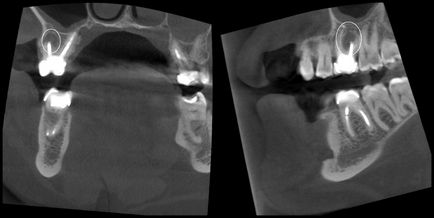

Minősége gyökértömés (töltési) csatornák és a jelenléte cisztás folyamatok körül tetejét a fogak

A perforáció a foggyökér és a ciszták keletkezését mezhkornevyh